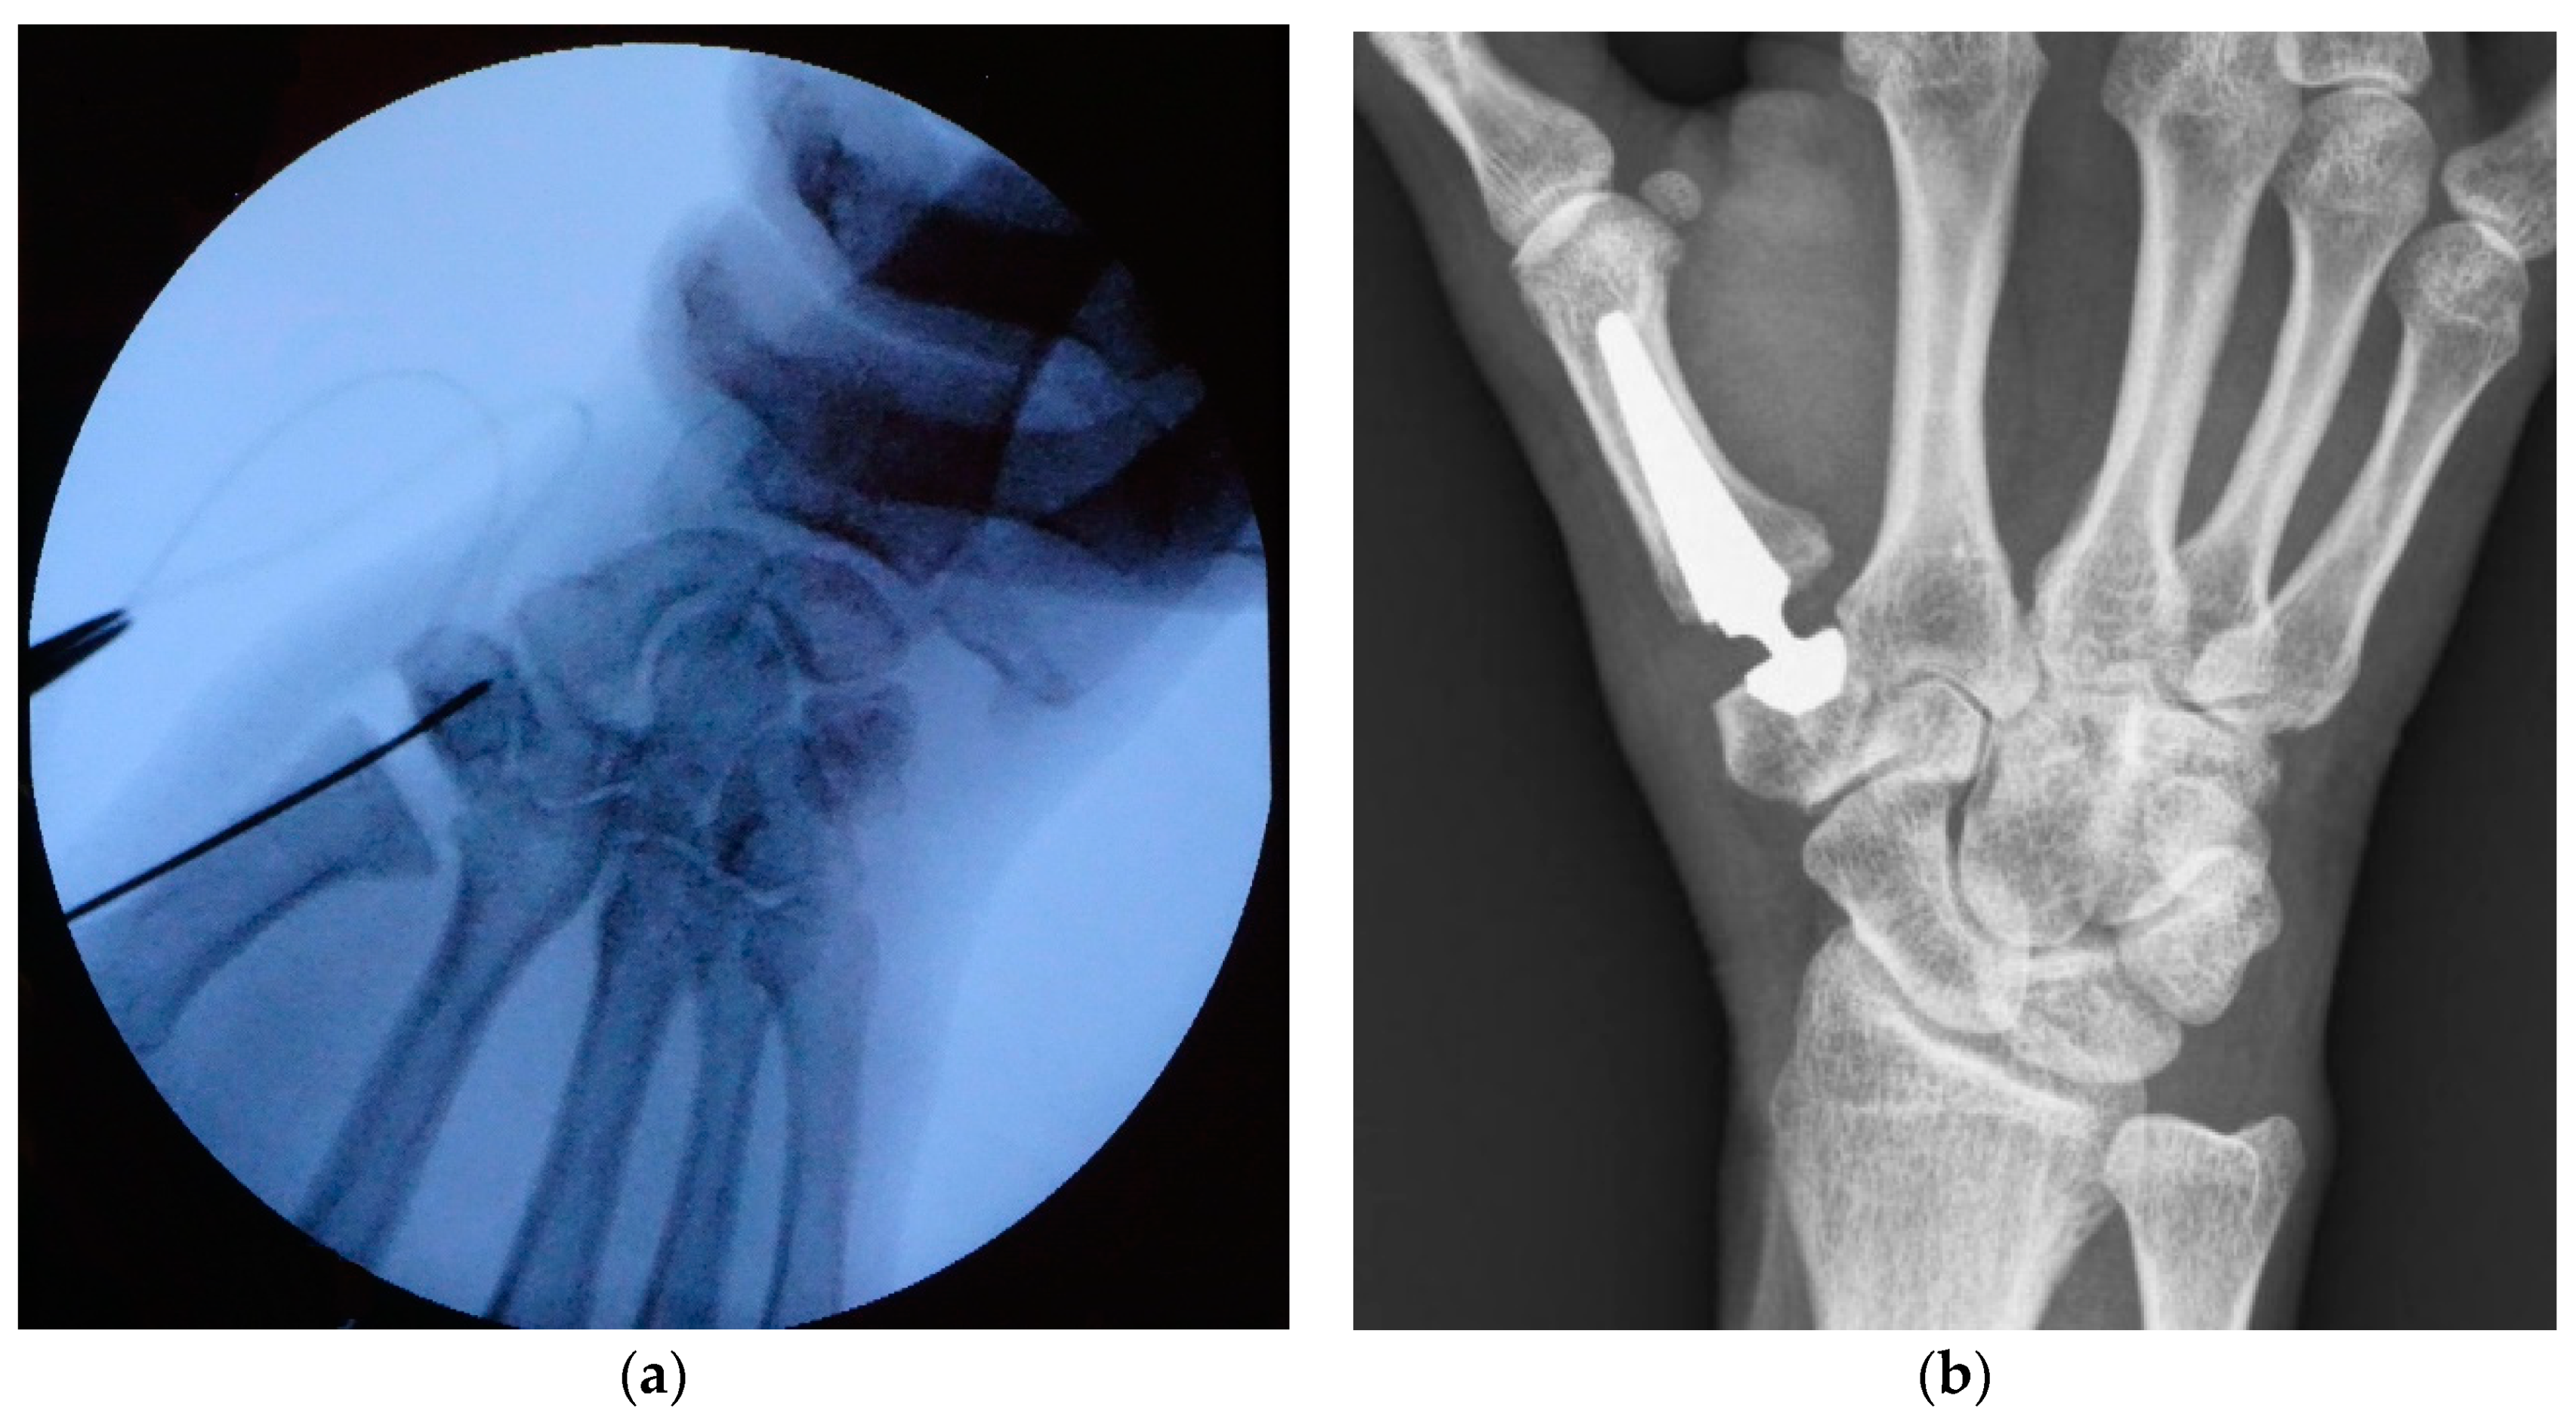

2.1. Surgical Technique